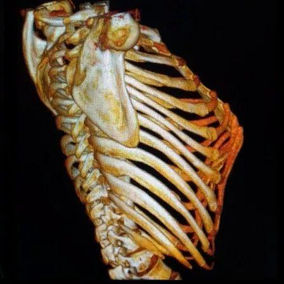

After a preoperative examination, it is observed that the patient's anterior chest wall protruded severely, reaching its peak at the xiphoid process, which presented as a 90-degree angle when viewed from the side. The heart is displaced to the right chest cavity, and the torso is severely deformed, characterized by a broad chest and a noticeably narrowed waist and abdominal area. The narrowing is most pronounced above the pelvis. Moreover, a chest CT scan reveals two large cysts located between the heart and the anterior chest wall in the lower lobe of the left lung, measuring 7x8 cm and 9x10 cm respectively.

We developed and executed a personalized minimally invasive surgical treatment plan for the patient. The Wung procedure and the Wenlin procedure was performed during the operation. First, a 3 cm longitudinal incision was made on the left chest wall to insert a thoracoscope, which was used to explore and remove the cysts on the left lung. Second, another 3 cm incision was made on the right chest wall and two passage tunnels were constructed for the bars between these two incisions. A third tunnel was then constructed near the costal arch, and three pre-shaped bars were inserted into the tunnels to correct the deformity. Lastly, the bars were securely fixed, and the incisions were sutured. The surgery was successfully completed in 2 hours, effectively eliminating the malformation and restoring the chest wall to an almost normal appearance.